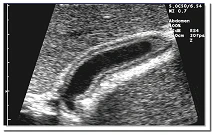

Eine volldigitale Technologie ermöglicht feinste Detail- und Kontrastauflösung der Gallenblasenwandschichten.